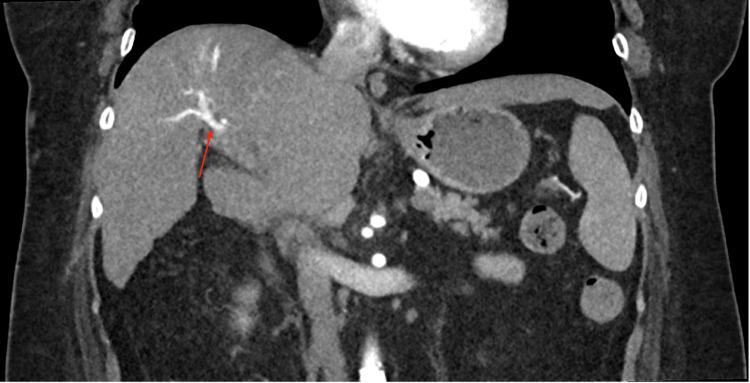

Hepatocellular carcinoma (HCC) is a complication of end stage liver disease. Even rarer is right atrial tumor thrombus burden due to HCC. Common metastatic sites of HCC in descending order are lung, peritoneum, and bone. We present a patient with liver cirrhosis due to nonalcoholic fatty liver disease (NAFLD) admitted due to incidental finding of right atrial thrombus on echocardiography after missing HCC surveillance for four years. Patient received a computed tomography (CT) scan that showed an inconclusive liver lesion despite two liver biopsies, and patient was incidentally found to have clear cell HCC diagnosed after right hepatectomy. Right atrial thrombus was treated with surgical thrombectomy and pathology showed necrotic HCC thrombi in right atrium with bile pigment. Due to the possibility of tumor growth with extrahepatic manifestations, screening in compensated cirrhosis is essential.

摘要

肝细胞癌(HCC)是终末期肝病的一种并发症。因HCC导致右心房肿瘤血栓负荷的情况更为罕见。HCC常见的转移部位依次为肺、腹膜和骨。我们报告一例因非酒精性脂肪性肝病(NAFLD)导致肝硬化的患者,该患者在漏查HCC四年后,因超声心动图偶然发现右心房血栓而入院。患者接受了计算机断层扫描(CT),尽管进行了两次肝脏活检,但肝脏病变仍不明确,患者在右肝切除术后偶然被诊断为透明细胞HCC。右心房血栓通过手术取栓治疗,病理显示右心房有坏死的HCC血栓伴胆色素。由于肿瘤有肝外表现生长的可能性,对代偿期肝硬化患者进行筛查至关重要。